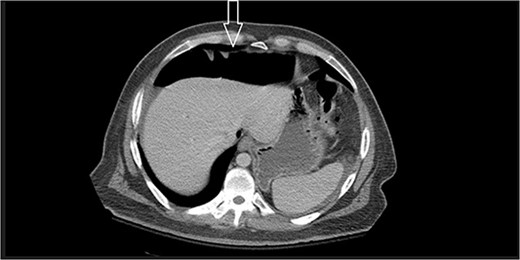

Dietary consultation started him on a gastroparesis diet where he progressed well. Upon hospital discharge CT showed a moderate volume of pneumoperitoneum with a small volume of perihepatic and perisplenic ascites. No areas of focal bowel wall thickening were noted (see Fig. 4).

Similar appearance of moderate volume pneumoperitoneum compared with last CT.